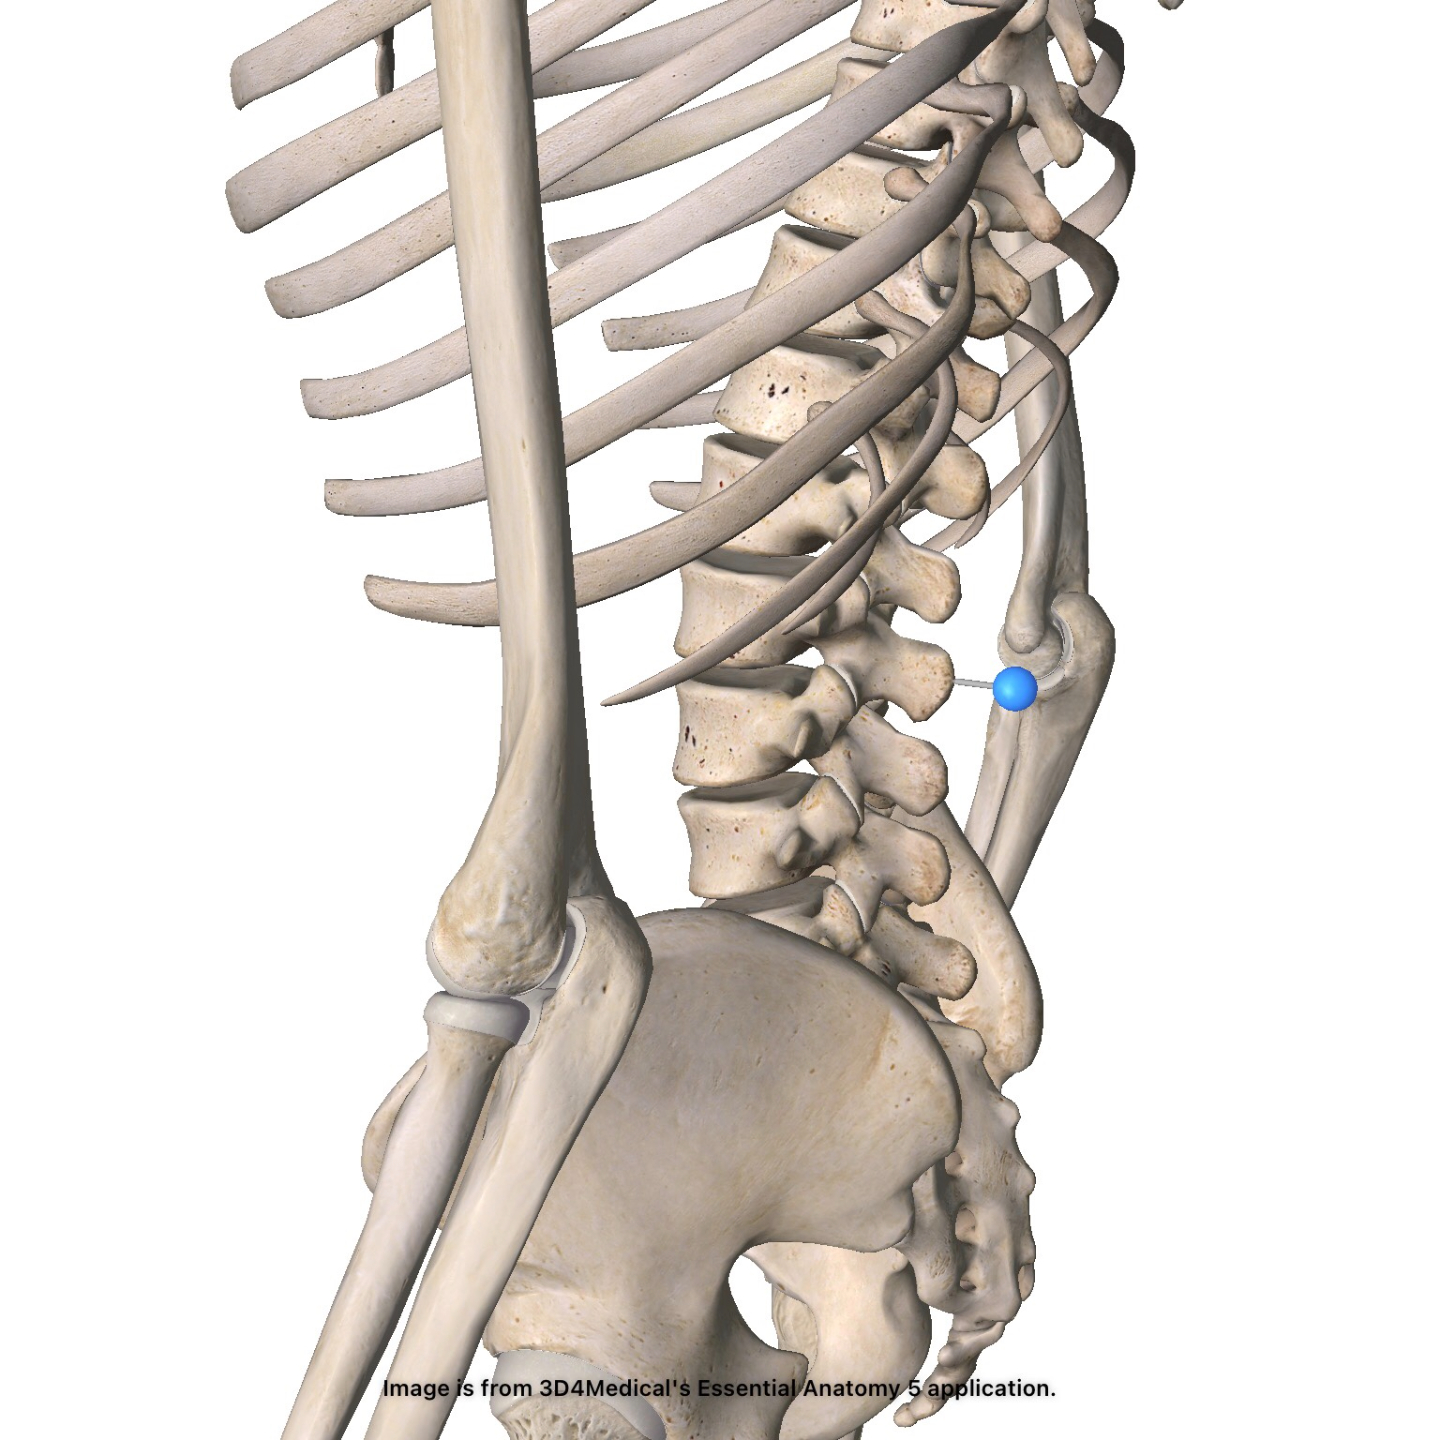

Back Injuries

Check out our one-of-a-kind diagnostic dashboard! Learn more about multiple orthopedic back injuries - the who, what, when, where, and how's.

Diagnostic Dashboard

Spondylolysis

Low Back Pain